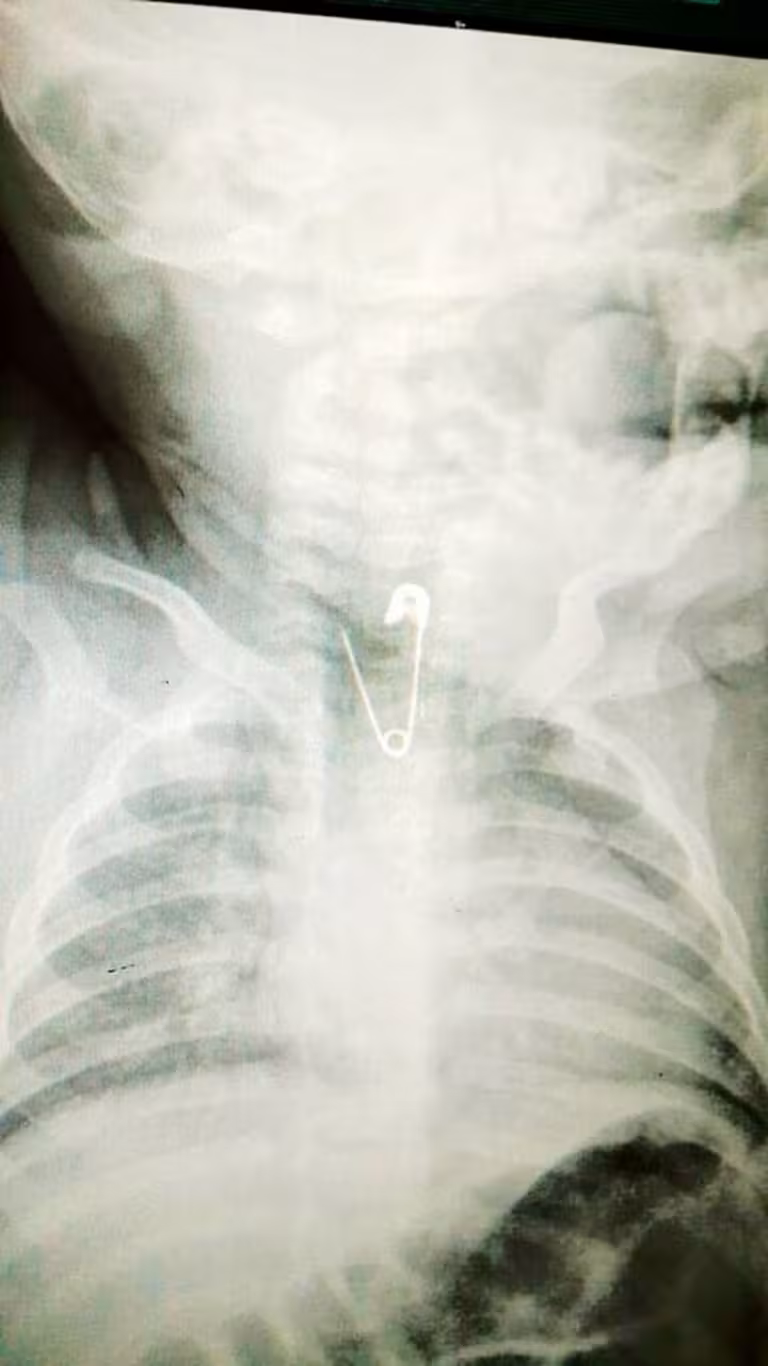

Небезпечні ігри: у Львова 6-місячна дитина проковтнула розкриту шпильку

У Львові у лікарню швидкої медичної допомоги привезли 6-місячну дівчинку, в стравоході якої застрягла розкрита шпилька. Причому, застрягла вона гострими кінцями вгору, так що витягнути її назад не було ніякої можливості. Дівчинка задихалася, кашляла і від будь-якого неправильного руху могла померти, повідомляють Факти.

Шпилька застрягла у стравоході.

Як виявилося, дитина бавилася хрестиком на ланцюжку. Хрестик висів на шпильці завдовжки, майже, два сантиметри. В якийсь момент, вона розстібнулась, хрестик випав, а шпилька залишилась у руках дитини. Дівчинка взяла її до рота і проковтнула. Батьки одразу ж звернулися до медиків.